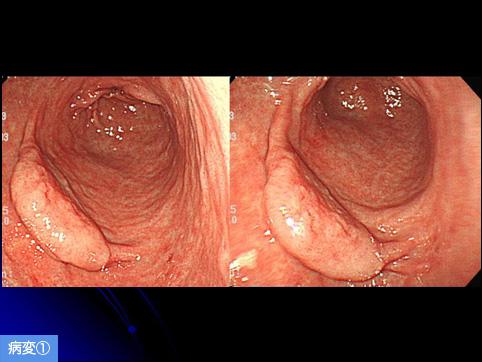

疾病(病理主体)的分类良性上皮性肿瘤/腺瘤

部位(按器官分)胃(部位)/前庭

肿瘤的肉眼分类0型(表在型)/IIa型(IIa)

肿瘤最大直径20~24

多发性肿瘤(同一器官)有(同时性)